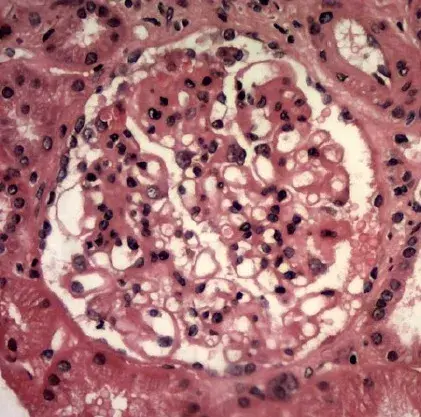

Es posible identificar un glomérulo con rotura de la membrana basal glomerular, con crecimiento celular en el espacio de Bowman (flecha blanca), células gigantes multinucleadas (estrella) y ruptura de la cápsula de Bowman (flecha negra) (tinción PAS; 400×). PAS, ácido periódico-Schiff.

La biopsia renal reveló GN (glomerulonefritis) crescéntica necrotizante difusa sin hipercelularidad endocapilar. Algunos raros glomérulos contenían células gigantes multinucleadas.

La evaluación de la microscopía de luz puede ayudar en la diferenciación entre casos de **GN por anti-MBG** y casos de **GN-ANCA**, ya que en la GN por anti-MBG no se observa hipercelularidad endocapilar y se puede identificar la presencia de células gigantes multinucleadas. Estas células gigantes multinucleadas resultan de la naturaleza explosiva y la rápida destrucción de los glomérulos observada en la anti-MBG.